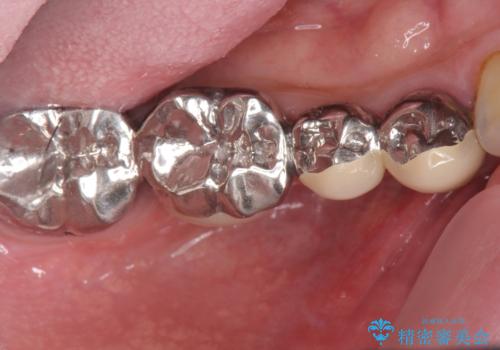

- 右下に入れた長いブリッジが噛むといたみ、改善を希望され来院されました。

長いブリッジは支台となる歯の過大な負担となることが多く、歯の破折や揺れ・痛みの原因となり得ます。

支台を増やし、残った歯の負担を減らし守るために欠損部位にインプラントを埋入し咬合力の負担に対応できる環境を整えます。